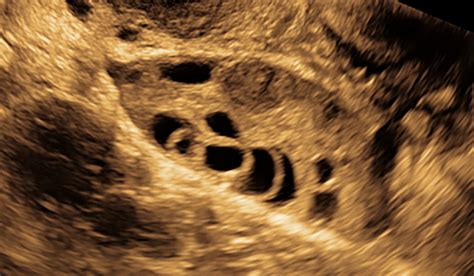

The Antral Follicle Count refers to the number of small follicles (2-10 mm in diameter) visible in the ovaries during an early follicular phase ultrasound. These follicles are crucial because they represent the pool of eggs that could potentially mature and be released during the menstrual cycle. The count is usually performed between days 2 and 4 of the menstrual cycle to ensure accuracy.

• Procedure: A transvaginal ultrasound probe is inserted into the vagina to get a clear view of the ovaries.

• Counting Follicles: The ultrasound technician counts the number of follicles in each ovary that measure between 2 and 10 mm in diameter.